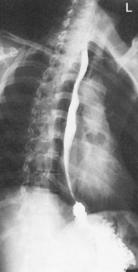

• Patient should be on side a minimum of 5 minutes before exposure; 10 to 20 minutes is preferred.

• Patient on side (on decubitus board or support to elevate downside abdomen), knees partially flexed, arms up near head

• Adjust patient and stretcher so center of IR and table (and CR) is approximately 2″ (5 cm) above level of iliac crest (to include diaphragm)

• Adjust height of IR to ensure that upside of abdomen is included for possible free air

• Patient supine (on decubitus board or support to elevate posterior abdomen), side against table, arms above head

• Secure stretcher (lock wheels)

• Center of IR and table (and CR) at level of iliac crest (2″ above iliac crest to include diaphragm)

• Adjust height of IR to align midcoronal plane to centerline of IR

• Immobilize arms above head (use stockinette, Ace bandage, tape, or sandbags).